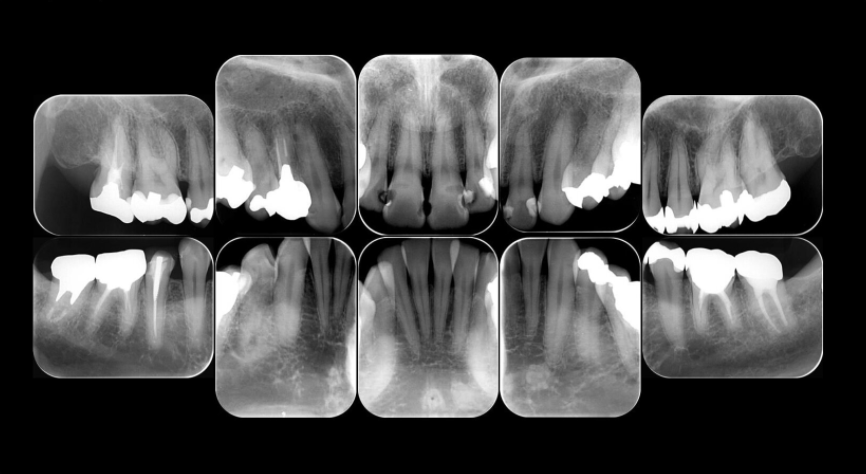

最大14部位のレントゲン検査

虫歯の有無・歯髄の有無・歯槽骨の吸収状態・病巣など細部を確認できます。

レントゲン10枚法または14枚法